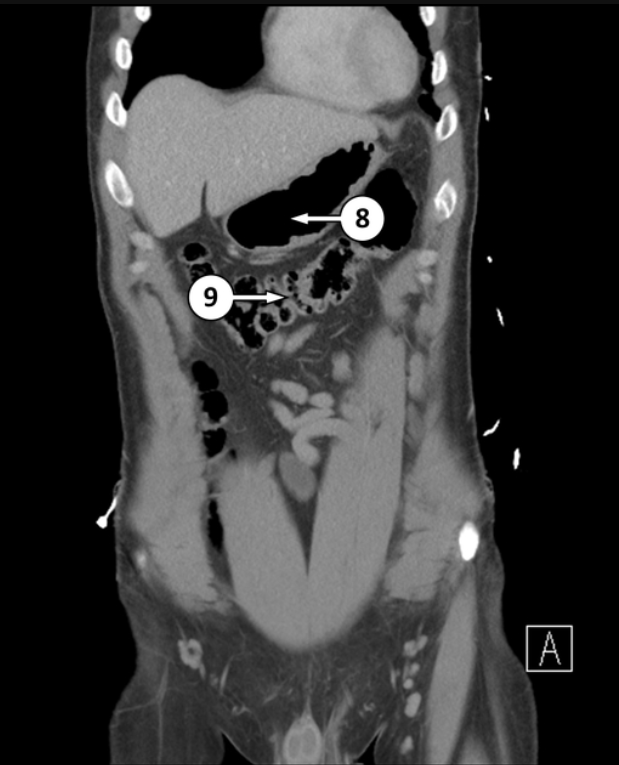

Please label what 8 and 9 is, and what type of epithelium they are

Body of stomach, simple columnar with parietal and chief cells

Transverse colon, simple columnar